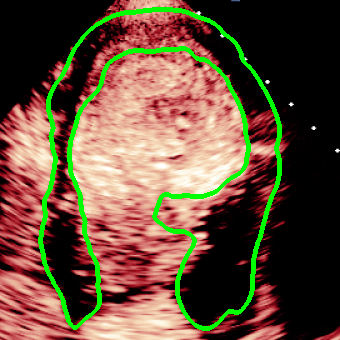

For variations caused by low quality images such as those of low resolution or significant artifacts, however, the unique ground truth may not be available. Take the myocardial segmentation task of Myocardial Contrast Echocardiography (MCE) as an example. An inter-observer experiment was conducted among five experienced cardiologists, and Fig. 1(a)(b) visualize the annotations of two images from three of these cardiologists. It can be seen that the labels by different cardiologists vary significantly, especially in locations where the intensity information of myocardium is very similar to the background. Table 1 shows the average Dice of the annotation of each cardiologist, using one of the others’ as the ground truth, over 180 images. We can observe that none of the Dice is above 0.9, some even under 0.8, confirming significant variations among the annotations. In this case, as the variations are caused by the image quality, even these cardiologists cannot tell which annotation is better than others, and a majority vote for ground truth would not make sense sometimes as can be seen in Fig. 1(c)(d). For this reason, we cannot obtain a unique ground truth in the evaluation process and the traditional metrics such as Dice and IoU cannot be used.